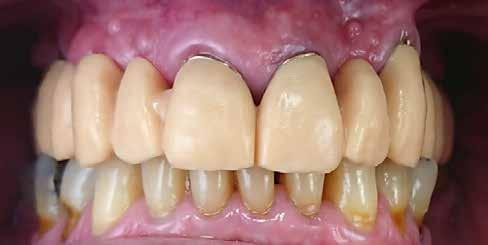

Az extrahálás és az új mosoly

A fogak extrahálása és az alveoláris plasztika teljes narkózis mellett történt meg, így teremtve ideális helyzetet a protetikai ellátáshoz. A műtéti beavatkozás után a páciens az ideglenes fogsorral távozott. Egy héttel később jött kontrollra. Nemcsak látványra változott meg nagymértékben, hanem egyértelműen magabiztosabb és önbizalommal teli volt a fellépése (12. ábra)

Összegzés

Az elsődleges terápiás szakasz kulcsfontosságú volt a teljes rehabilitáció szempontjából. A páciensnek nem csak szép, esztétikus mosolyt kölcsönzött, hanem életminőségének javulását is hozta (13. ábra). A Digital Denture folyamatnak köszönhetően a kezelés ráfordításai is alacsonyak voltak. A fiatal nő messzemenően boldog, magabiztos és motivált a következő lépéshez.